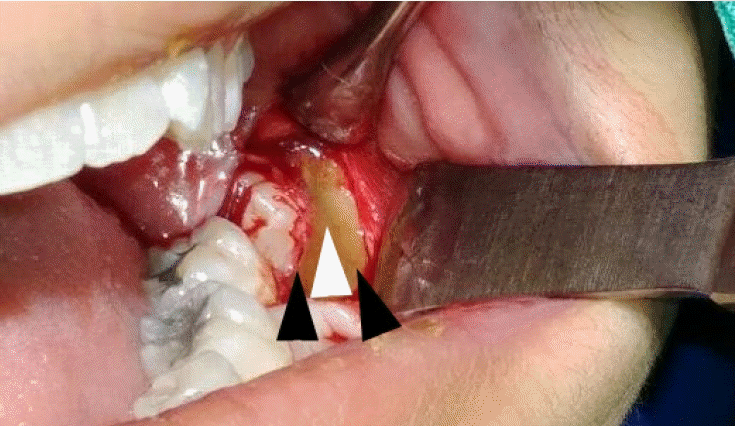

Figure 2.

Alternating bands of blue-gray and yellow discoloration of the alveolar bone observed during flap reflection for surgical extraction of the left mandibular impacted third molar.